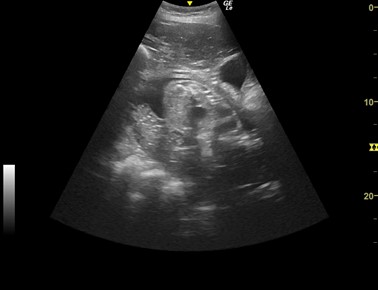

4 胎芽がうつる

2018年8月2日(妊娠10週目)ついに「胎芽」が写る

妊娠検査薬は陽性を示し「レンボー」が妊娠していることは、ほぼ間違いないことが分かっていた2018年8月2日、これまでの取組が結果となる日が来ました。ついに「胎芽」を写すことに成功しました。妊娠10週目のことでした。

「胎芽」とは妊娠初期のまだ心臓の拍動も確認できない胎児の状態をいいます。この時わずか12㎜の大きさです。これほど妊娠初期の段階の画像を残すことが出来たのは、学術的にもとても大きな成果であったと思います。

5 胎児の成長記録

ハズバンダリートレーニングによる超音波検査の素晴らしいところは、動物にとってストレスが少ないことです。また、写真では分かりにくいのですが、「レンボー」は検査が嫌になれば、自ら検査から逃れることが出来る環境で検査を実施しています。そのため、毎週一回の超音波検査を継続し、胎児の成長を記録することが出来ました。ここでは、その一部を紹介します。

2019年10月11日(妊娠20週目)顔が写る

2019年10月30日(妊娠23週目)全身が写る